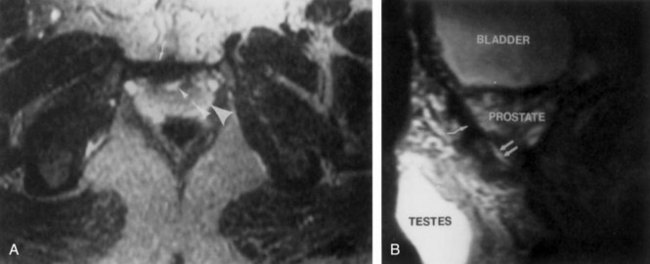

The male genital defect is severe and is probably the most troublesome aspect of the surgical reconstruction, independent of the decision whether to treat with modern staged closure, combined closure, or a form of urinary diversion (Fig. 124–6). Formerly, it was thought that the individual corpora cavernosa were of normal caliber but appeared shorter because of the wide separation of the crural attachments, the prominent dorsal chordee, and the shortened urethral groove. However, Silver and colleagues (1997b) described the genital defect for the first time in bladder exstrophy in greater detail. MRI was used in adult men with bladder exstrophy and compared with results for age- and race-matched controls. They found that the anterior corporal length of male patients with bladder exstrophy was almost 50% shorter than that of normal controls (Fig. 124–7). However, although the posterior length of the corporal body was the same as in age-matched controls, the diameter of the posterior corporal segment was greater than in normal controls. It was also found on MRI that the diastasis of the symphysis pubis increased the intrasymphyseal and intercorporal distances, but the angle between the corpora cavernosa was unchanged because the corporal bodies were separated in a parallel fashion. Therefore the penis appears short not only because of the diastasis of the pubic symphysis, as thought in the past, but also because of marked congenital deficiency of anterior corporal tissue (Silver et al, 1997b). In a recent surgical anatomic study by Perovic and Djinovic (2007), precise description of the penile defect included (1) corporal bodies separated and triangular in shape; (2) a long convex ventral surface and a short wedge-shaped dorsal surface; and (3) neurovascular bundle length determined by its lie on the individual corporal bodies.

Figure 124–7 Separation of the pubic bones in men with classic exstrophy combined with the congenital deficiency of the anterior corporal tissue leads to the shorter appearance of the penis. aCC, corpora cavernosa sustended angle; ACL, anterior corporal length; Cdiam, corpus cavernosum diameter; ICD, intercorporal distance; ISD, intersymphyseal distance; PCL, posterior corporal length; TCL, total corporal length.